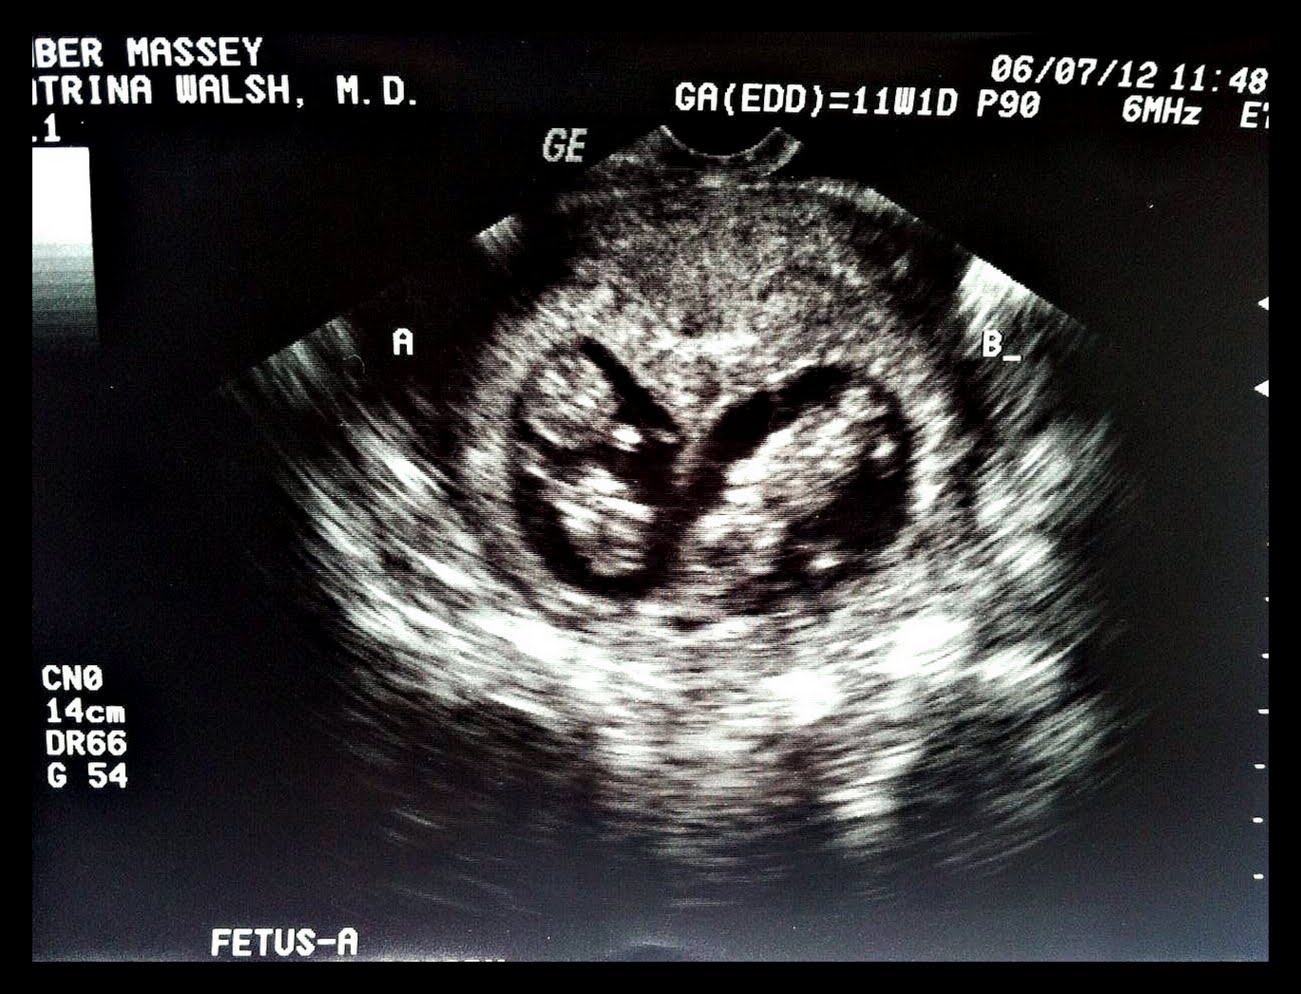

Number ONE.. and TWO

Thats right! Our house is growing into an instant family of four! Due date..? December 26th. Christmas Babies! Well, sort of. My doctor (the most amazing woman, ever!) told Jordan and I that if I am still carrying these two around December 5th, she is going to tie me to her car and run me around the block. So we expect the first week in December these sweet little ones will be here. Plus positive to that? Most likely- actually, abut 98% sure– I will be having a C-Section, and even with the 5-7 days in the hospital post-op, we’ll be home by Christmas. Yayayayaya!

There they ARE! YES.. you are seeing two little babies in there. Baby A and Baby B- strong and healthy! We got to see them last Thursday- for the 3rd..err, 4th time. We have been spoiled with sonograms and have gotten to take a peek every time we go into the doctor’s office. Heartbeats have been on the perfect end of perfect: (A)173bmp and (B)180bpm- simply ‘perfect’..I’m bias for sure.

Baby A is smaller than Baby B, and has been from the beginning. First time we got to see the little ones was around 7 weeks. Baby B was measuring 2 days larger than Baby A, so the doctor brought us back a week later (8 weeks) to make sure everyone in there was growing well. Baby A had caught up an entire day! Now they are only 1 day apart- wait to go my little fighter. Twins can be up to 3 days apart in utero and still be of normal growth. Babies are still measuring 1 day apart.

Number 4.) This last time we got to see the babies- Baby B was doing the baby jig, bouncing all over the place and literally looked as if it was waving at the screen. So precious. I was speechless, like someone had knocked the wind out of me. Like nothing I had ever seen before.. this was the first time either of us had seen them move at all. It’s movement was kind of like the scene in Look Who’s Talking where the baby finds its hand while he is still inside the womb.. and when he moves its like there are a multiple all at once. SO cool.